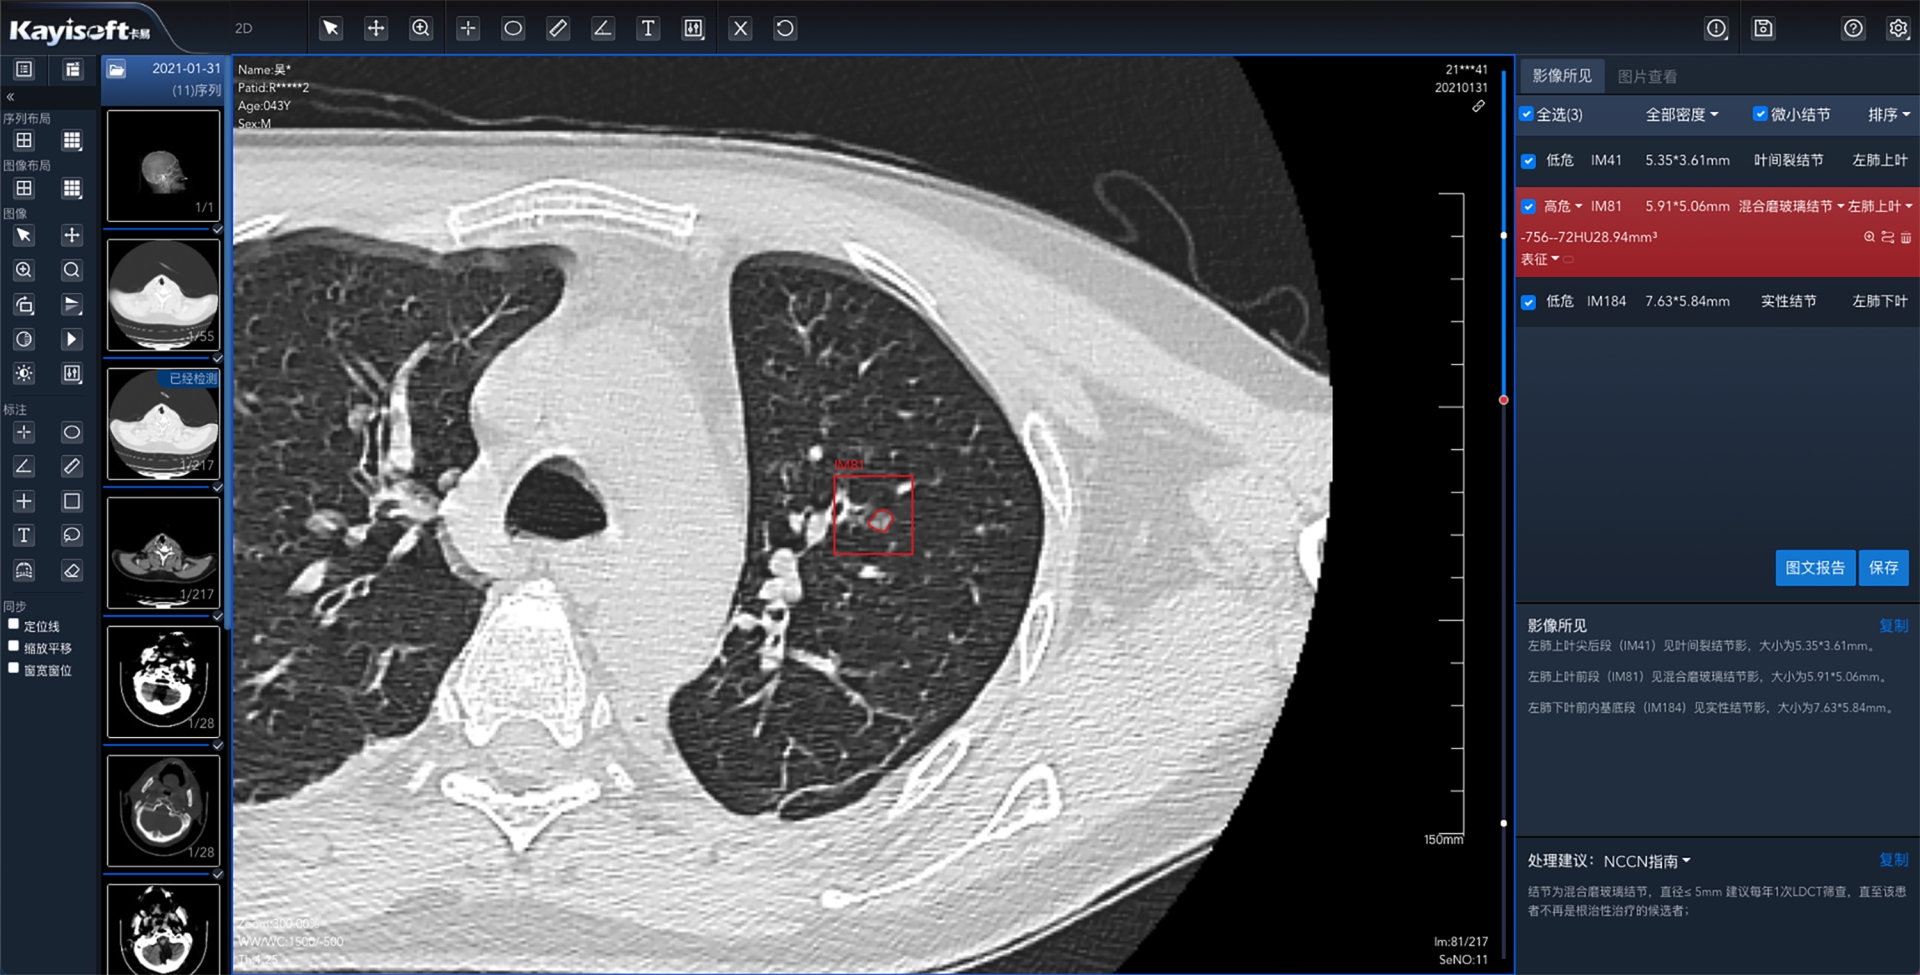

基于全市区域影像云肺结节AI分析服务是通过温州市医学影像云平台完成区域医疗影像数据云化管理数据统一采集,实现以数据为基础,结合AI分析服务肺结节智能标注,在短时间内分析完成并生成“AI结构化报告”和“指南参考”来协助诊断医生参考,提高工作效率。

AI分析服务+影像云的优势组合,能够统筹服务器资源,统一维护便于管理;资源分配更加均匀,使得基层医院也能具备大型三甲医院的诊断能力;各医院可通过基于影像云肺结节AI分析服务实时调阅影像,针对温州市范围内的肺结节病例进行量化指标的统计分析。

本产品在辅助医师临床诊断、体检筛查、辅助科研等诸多领域都有着相当大的应用价值和发展前景,有利于区域管理手段现代化,为未来AI的动态跟踪和大数据分析提供强有力的基础支撑。